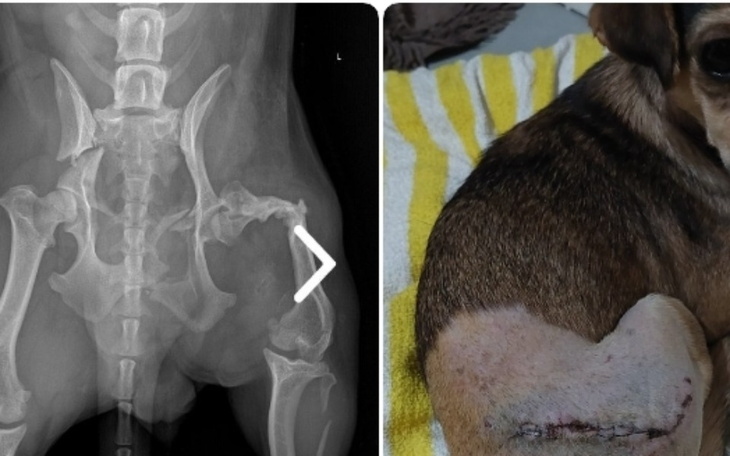

Simonka walczy o to aby być psem sprawnym😥. Ta dzielna mała sunia już kiedyś uległa wypadkowi w wyniku którego ma krótszą ,sztywną łapkę.Obecnie ma złamaną miednicę ,która została operacyjnie złożona na płytke i śruby.Poskładano również odłamki kości. Na ten czas Simonka nie chodzi gdyż to prawa strona -lewą już wcześniej ma niesprawną😥.Przyjechała już niestety ze starymi złamaniami,bojącą się i uciekającą przed człowiekiem.Do tej pory używała tylko prawej tylnej łapki i biodra obecnie kiedy właśnie prawa strona jest połamana ,jest psem inwalidą nie mogącym chodzić.Oprócz zabiegu potrzebna będzie intensywną rehabilitacja. Koszt pierwszej no nocnej wizyty +zdjęcia ok.500 zł,zabieg i pobyt w szpitaliku ok.3,500.Do tego koszt rehabilitacji.Bardzo proszę o każdą złotówkę🙏🙏🙏